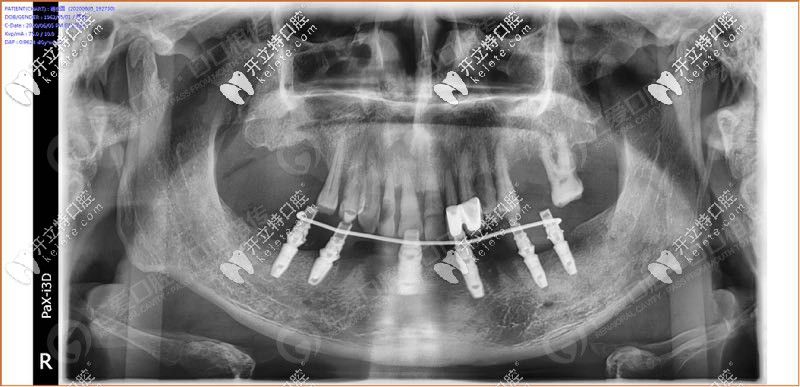

經(jīng)過(guò)我院種植醫(yī)生面診,拍片檢查發(fā)現(xiàn),31、32 、33、 34顆牙松動(dòng)(3度),43顆牙也松動(dòng)了, 44、45多年前做了烤瓷牙修復(fù),其余牙缺失。

具體設(shè)計(jì)方案:拔除下半口松動(dòng)牙后,在33、34、36、43、44、46牙窩采用種植導(dǎo)板植入性價(jià)比高的登騰種植體,當(dāng)天帶上牙冠,實(shí)現(xiàn)“當(dāng)天種牙,當(dāng)天用”。

手術(shù)時(shí),我院采用的種植導(dǎo)板技術(shù),術(shù)前設(shè)計(jì),種植體植入方向、位置、角度、深度等一目了然,導(dǎo)板輔助將種植植入到理想位置,有效避開(kāi)神經(jīng)、血管等危險(xiǎn)區(qū)域,同時(shí)也大大縮短手術(shù)時(shí)間,在拔牙窩即拔即種,沒(méi)有切口或切小口,愈合快。

順利植入6顆種植體后,把過(guò)渡性臨時(shí)假牙固定到下頜的種植體上實(shí)現(xiàn)了當(dāng)天種牙,當(dāng)天用的即刻負(fù)重種植牙。